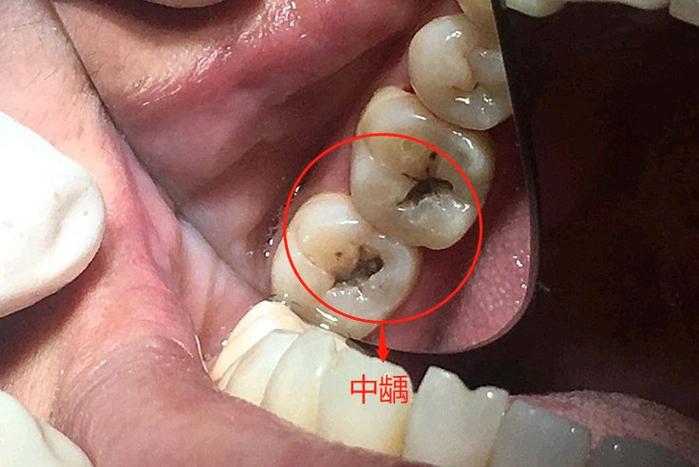

龋牙的发展过程是一个从浅到深、从无症状到疼痛的渐进过程,根据病变深度,临床上将龋洞分为浅龋、中龋和深龋,浅龋病变仅局限于牙釉质层,患者通常无明显自觉症状,仅在口腔检查时发现牙齿表面有色泽改变,呈白垩色或黄褐色斑点,探诊时有粗糙感,牙齿脱矿尚处于早期,及时干预可以逆转,若未得到处理,病变继续向深部发展,突破牙釉质到达牙本质浅层,即为中龋,患者对冷、热、甜、酸刺激可出现一过性、尖锐的疼痛,刺激去除后疼痛立即消失,探诊时可有明显的龋洞,洞底较软,当病变深及牙本质深层接近牙髓时,称为深龋,患者对各种刺激的疼痛加剧,持续时间延长,并可出现自发性疼痛、放射痛等症状,有时冷热刺激可激发剧烈疼痛,细菌毒素或感染物质可能通过牙本质小管刺激牙髓,引发牙髓炎,甚至发展为根尖周炎,出现牙龈肿胀、面部肿胀等严重并发症。

龋牙的临床表现多种多样,除了上述的色泽改变、形成龋洞外,还可表现为牙齿实质性缺损、对冷热酸甜刺激敏感、咀嚼食物时疼痛、口腔异味等,根据龋损的解剖形态和发生部位,还可将龋牙分为多种类型,如光滑面龋(发生在牙齿唇、颊、舌、腭面)、窝沟龋(发生在牙齿咬合面的窝沟裂隙)、根面龋(发生在牙根表面,多见于牙龈退缩的老年人)、线形釉质龋(多发于邻面,呈条状)等,不同类型的龋牙,其治疗方法和预后也有所不同。

| 中龋 | 牙本质浅层 | 形成明显龋洞,洞底较软 | 对冷、热、甜、酸刺激一过性疼痛 |